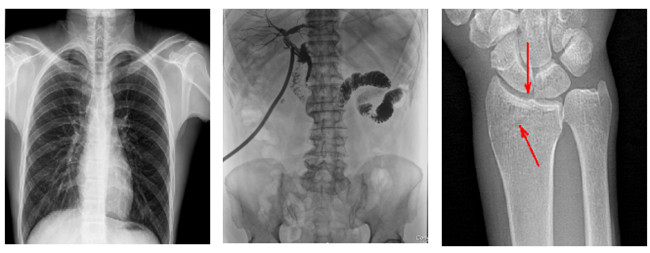

普利德多功能懸吊動態(tài)DR,搭載100μm高品質(zhì)動態(tài)平板探測器,不僅滿足常規(guī)的數(shù)字化X線全身攝影需求,同時還擁有數(shù)字攝影、數(shù)字透視、數(shù)字造影、全景拼接等多種功能,極大地拓展了X線檢查在臨床應用范圍,為醫(yī)院臨床應用帶來更多實用價值?;诎傥⑵桨宓母咔宄上?,圖像清晰度與分辨率更高,可滿足不同檢查部位對細節(jié)成像的高品質(zhì)要求,在胸腹部、脊柱等復雜骨骼和軟組織的攝片上應用,更便于觀察隱匿性病灶,精準識別疑難病癥。

不同于靜態(tài)DR拍攝隱匿性病灶時,由于組織重疊病灶難辨,耗費時間更長且易漏診、誤診,普利德多功能懸吊動態(tài)DR可通過動態(tài)實時連續(xù)成像,對于重疊部位病灶或者易被遮擋的病灶進行多角度動態(tài)觀察,毫秒級時間內(nèi)實現(xiàn)動靜態(tài)轉(zhuǎn)換點片,快速、精準完成攝片。比如隱匿性肋骨骨折,可在透視下觀察患者的呼、吸過程,避開重疊影像,快速點片,保證檢查部位的病癥不被遺漏,實現(xiàn)精準診斷。